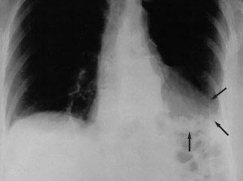

Cough and Dyspnea

Timothy J. Barreiro, DO; Anthony Pietropaoli, MD